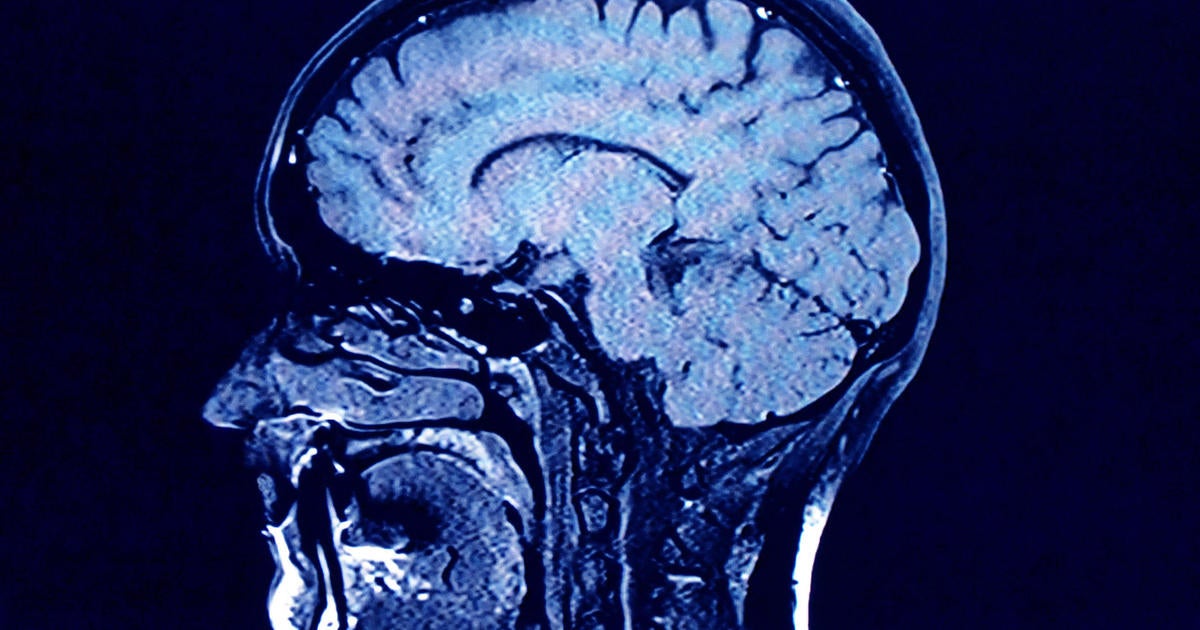

Human brains comprise greater concentrations of microplastics than different organs, in accordance with a brand new research, and the quantity seems to be rising over time.

Within the research, revealed Monday within the journal Nature Medication, College of New Mexico Well being Sciences researchers discovered microplastics in human brains have elevated 50% over the previous 8 years. Additionally they discovered that folks with dementia had as much as 10 instances as a lot plastic of their brains as everybody else.

The research in contrast liver, kidney and mind tissue samples from autopsies performed in 2016 and 2024, and located “considerably greater concentrations” within the 2024 mind tissue. The researchers additionally performed related evaluation on older and more moderen autopsies for individuals who died with confirmed dementia diagnoses, and located “far higher” concentrations.

Whereas it is unclear how particles are literally being transported into the mind, Campen mentioned the dimensions of the micro- and nanoplastics, measuring 200 nanometers or much less, aren’t a lot bigger than viruses and subsequently sufficiently small to cross the blood-brain barrier.